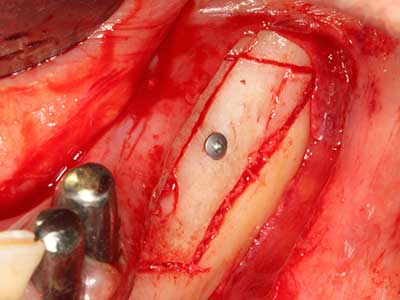

Пиезохирургията има допълнителни предимства при събиране на костни блокове. В допълнение към високата прецизност при остеотомията, описана по-горе, употребата на фините режещи накрайници значително намаляват загубата на материал. Голяма загуба на материал по време на събиране може да се очаква с дебелите накрайници, особено при употреба на борери Линдеман (Lakshmiganthan, Gokulanathan et al. 2012). Базалното разделяне, което е необходимо, особено за присадка на блок при ретромолар, е улеснено от специално създадени правоъгълни триони. В резултат на това, пиезохирургията е разглеждана като прецизна, улеснена и безопасна процедура за събиране на костни блокове в ретромоларното пространство (Happe 2007) (Фиг. 1-12).

Фиг. 1: Препарация на костно покритие с Piezomed (W&H Залцбург, Австрия).

Фиг. 3: Базалното разделяне на блока е по-лесно със специалните извити накрайници.